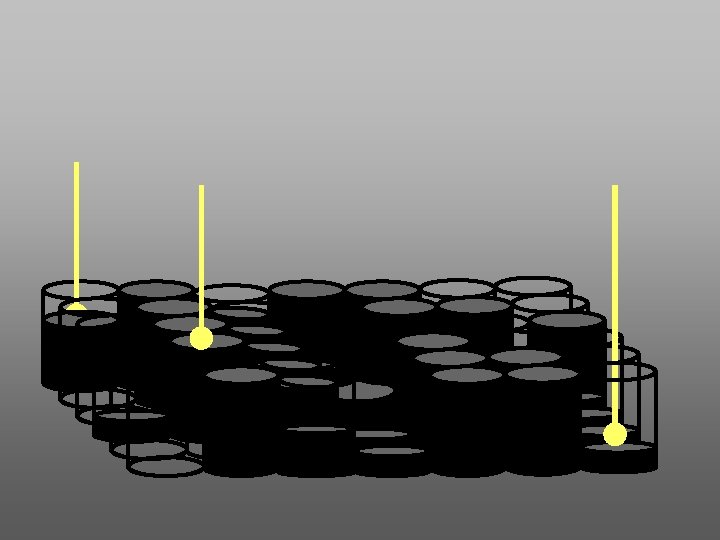

SISTEMA DIRECTO 1. EMISOR DE RAYOS “X” CONVENCIONAL 5 2. SENSOR ELECTRONICO CCD (CHARGE-COUPLED DEVICE) O CMOS-APS (COMPLEMENTARY METAL OXIDE SEMICONDUCTOR ACTIVE PIXEL SENSOR) 3. CONVERTIDOR DE INFORMACION ANALOGA A DIGITAL. 4. SOFTWARE (DICOM) 5. MONITOR 6. IMPRESORA 3 2 6 1